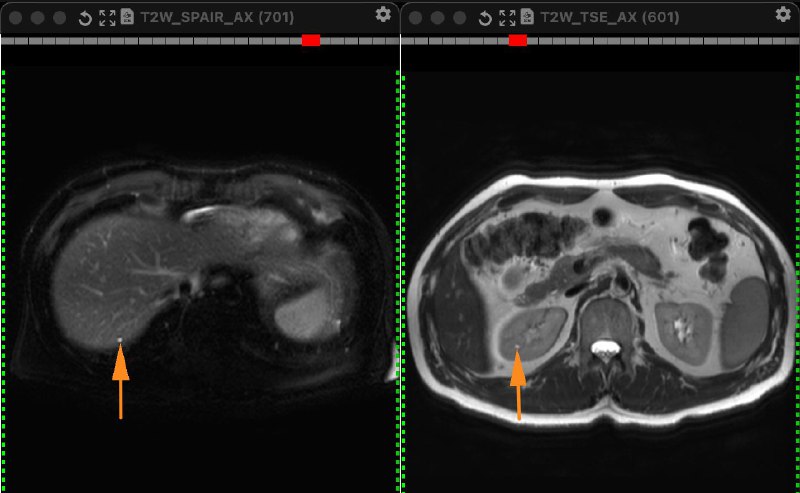

Замечаете такие?

Описываете такие?

Выносите в заключение?